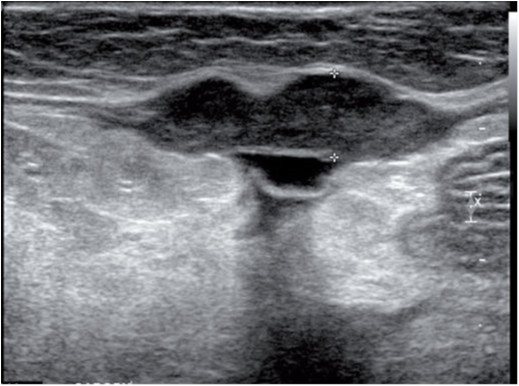

肱二头肌腱鞘炎是犬的常见疾病,但在猫并不常见,仅有一例关节窝发育不良公猫的相关病例报道。肱二头肌腱鞘炎表现为肱二头肌肌腱回声正常,腱鞘壁增厚肿胀,伴有无回声液体渗出,液体中漂浮有线性回声物。肱二头肌沟表面形状不规则。